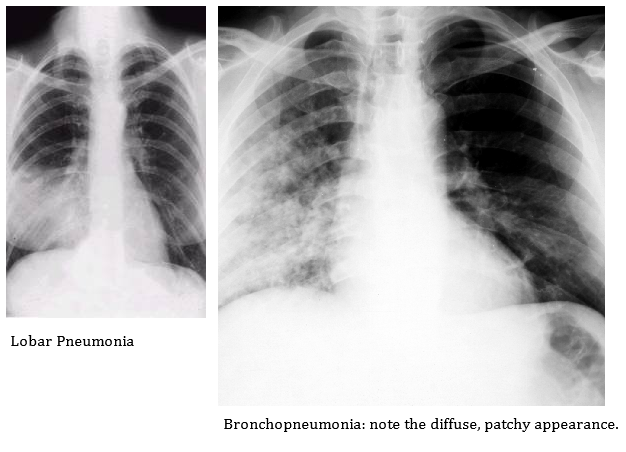

Pneumonia adalah : proses infeksi akut yang  mengenai jaringan paru-paru (alveoli). Berdasarkan letak anatomis dibagi menjadi 3 yaitu pneumonia lobaris, pneumonia lobularis (bronchopneumonia) dan pneumonia interstitialis (bronkiolitis).

Bronchopneumonia adalah proses infeksi akut yang menyerang bronkus paru.